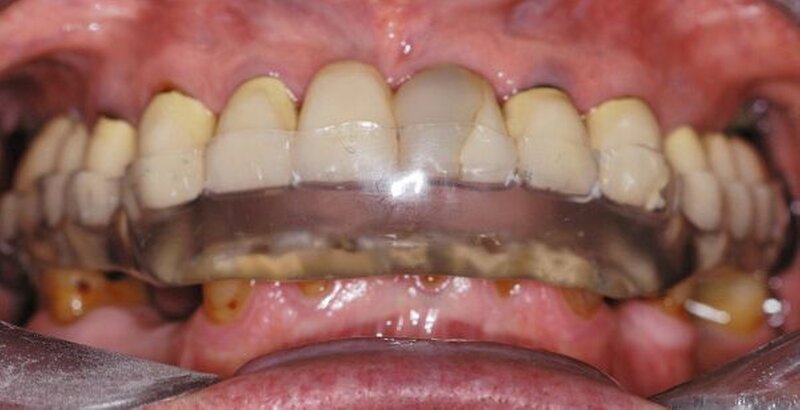

In der darauf folgenden Sitzung wurden alle Kronen und Brücken sowie die teleskopgetragene, partielle obere Prothese für einen Zeitraum von sieben Tagen zum Probetragen mittels eines Zements auf Zinkoxid-Eugenol-Basis eingegliedert. Dem Patienten sollte durch das Probetragen der Restaurationen beziehungsweise des angefertigten Zahnersatzes die Möglichkeit gegeben werden, sowohl die Funktion beim Essen und Sprechen als auch die Ästhetik im sozialen Umfeld zu testen. Ein erneutes Entnehmen der Restaurationen wäre – für den Fall notwendiger Korrekturen – somit ohne Weiteres möglich gewesen. Da der Patient sowohl die Funktion als auch die Ästhetik betreffend keine Änderungswünsche vorbrachte und auch keine neuerlichen Beschwerden aufgetreten waren, konnten die Restaurationen nach besagtem Tragezeitraum von sieben Tagen entnommen, gesäubert und mittels eines Glasionomerzements definitiv befestigt werden. Im Anschluss wurden erneut Situationsabformungen der Kiefer genommen und der Patient erhielt nach erneutem Checkbiss-Registrat, eine okklusal adjustierte Stabilisierungsschiene im Unterkiefer. Diese dient der Therapie der beschriebenen Bruxismusproblematik und gewährleistet einen langfristen Erfolg der eingegliederten prothetischen Restaurationen (Abbildungen 13a, 13b, 13c, 14, 15a, 15b, 15c).